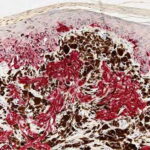

Pigmented Epithelioid Melanocytoma = ورم الخلايا الميلانية البشرواني المصطبغ